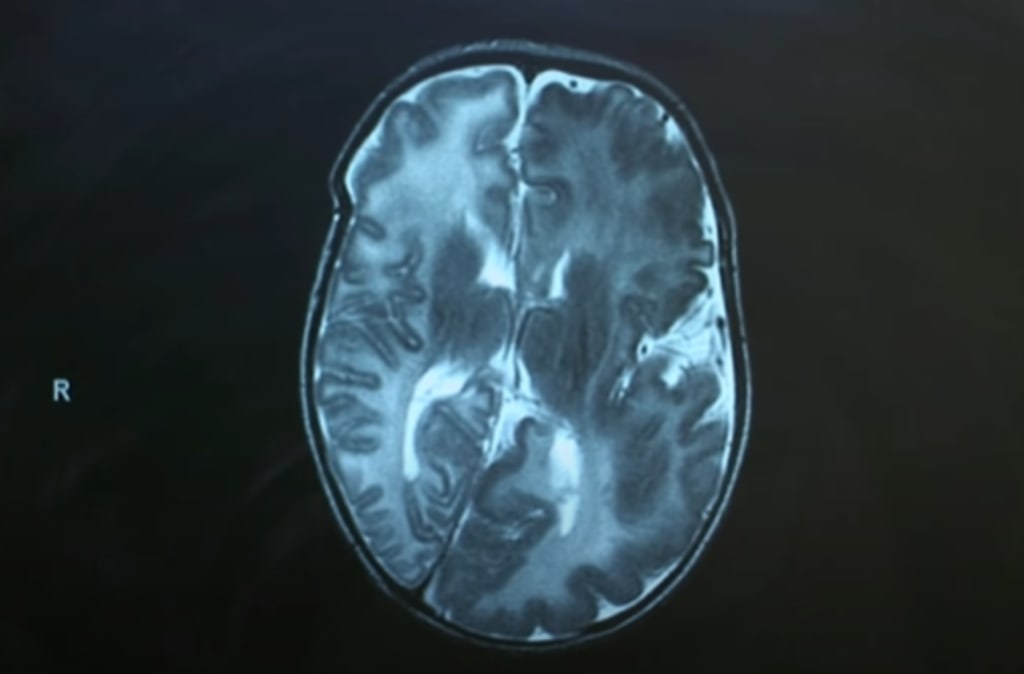

Day after day there were most tests ran on her and after about a week she was sent for an MRI and a CT scan. One of the doctors who was taking care of my sister came back to us with a diagnosis called Hemimegalencephal for short HME. This is a rare neurological condition in which one-half of the brain, or one side of the brain, is abnormally larger than the other. The structure of the brain on the affected side may be markedly abnormal or show only subtle changes and this is what had lead to her seizures. One side of the brain had actually travelled and pushed the normal side.

One of the doctors who was caring for Mollie took my parents into a little room just off of the intensive care unit, sat us down and he told us that having Hemimegalencephal was a condition that had pretty much in-controllable seizures and they didn't know what to say or what to do. The doctor said she may be able to have surgery but if that was the case then she would have to have her brain removed, and thats what happened to her, she had the left hand side of her brain removed.